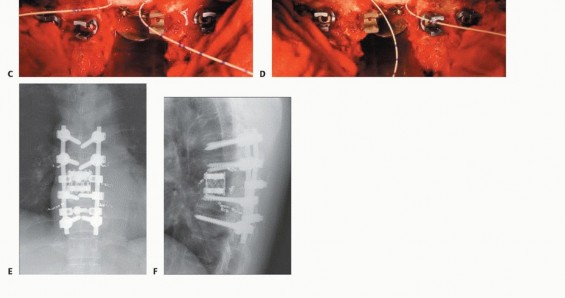

5. Anterior Reconstruction and Posterior Instrumentation

An anchor hole on the cut end of the remaining vertebra is made on each side to seat the graft. A vertebral spacer such as a titanium mesh cylinder cage with autograft, allograft, or cement(TECH FIG 6) is properly inserted to the anchor holes within the remaining healthy vertebrae. After checking the appropriate position of the vertebral spacer radiographically, the posterior instrumentation is adjusted to slightly compress the inserted vertebral spacer. By this “spinal shortening” procedure, the block cylinder is caught tightly, and the anteroposterior 360-degree spinal reconstruction is completed. 2,7 If two or three vertebrae are resected, it is recommended that the connector device be applied between the posterior rods and anterior spacer (artificial pedicle).

TECH FIG 6. A. A vertebral spacer is properly inserted to the anchor holes within the remaining healthy vertebrae. B. Schema of reconstruction (lateral view). C,D. After checking the appropriate position of the vertebral spacer radiographically, the posterior instrumentation is adjusted to slightly compress (10 mm in this case) the inserted vertebral spacer. E,F. Postoperative radiograph after spinal column shortening shows three pairs of preoperative embolization coils. (continued...)

TECH FIG 6. (continued...) G-I. Resection of two vertebrae. G. Bilateral artificial pedicles are placed. H,I. Postoperative radiographs of reconstruction with artificial pedicle.